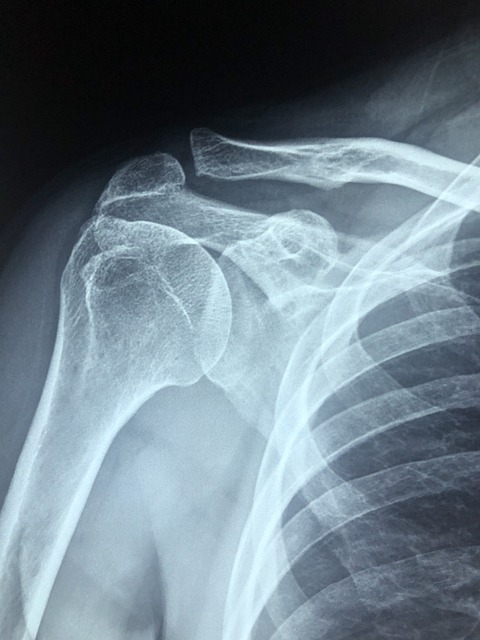

원인 2. 충돌증후군

충돌증후군은 팔을 올리거나 회전시킬 때, 어깨의 움직임과 안정성을 원조하는 회전근 힘줄이 견봉과 충돌하며 손상과 통증을 유발시키는 질환을 말 해요. 충돌증후군의 특징은 팔을 옆으로 어깨 높이만큼 올렸을 때 통증이 심해지고 제한이 느껴져요.

원인 7. 회전근개 파열

회전근개는 어깨에 자리한 회전근개의 파열이나 변신이 통증으로 발생하는 것이예요. 회전근개의 구조는 어깨와 팔을 연결하는 4개의 근육과 힘줄로 발생되어 있다는데 이 근육들의 탈바꿈이나 파열이 어깨 통증의 원인이 됩니다.

오십견은 어깨에 발생하는 자주 보이는 질병으로 보통 50살 전후에 생겨난다고 해서 오십견이라고 부른다고 해요. 오십견은 관절낭, 즉 어깨를 둘러싸고 있는 섬유 주머니에 유착과 염증이 일으켜서서 병이 나서하는 질환이고요.

오십견은 퇴행성 변환나 외주의 큰 충격으로도 병에 걸려이 되었는데 이때 통증은 참을수 없을 정도이예요. 통증이 대략적으로이냐면 바늘로 어깨를 찌르는 것 같은 격렬한 통증이 생기면서 어깨를 살아가는 반경이 좁아진다고 해요.